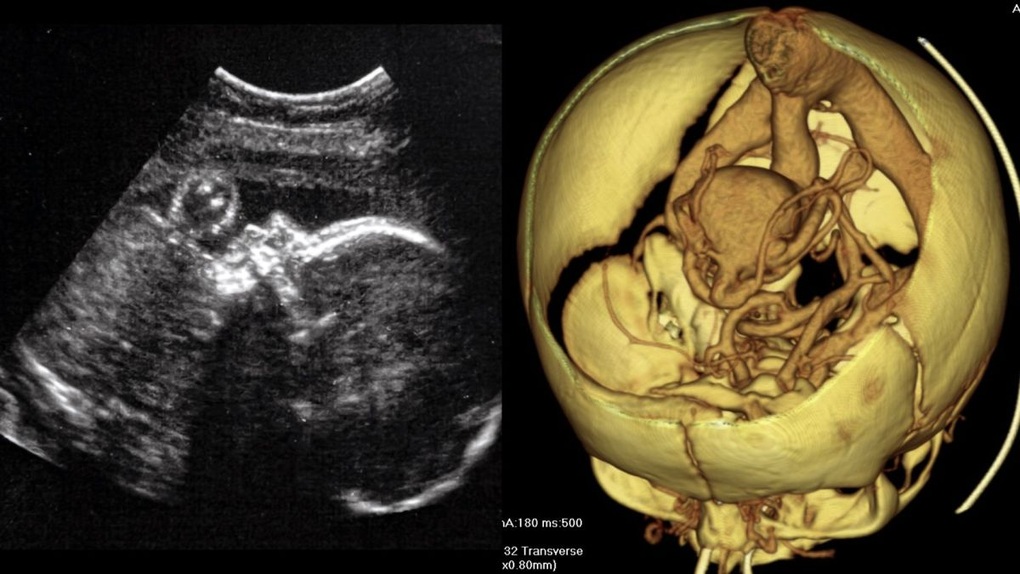

Ở những thai nhi mắc dị tật hiếm gặp được gọi là dị dạng tĩnh mạch Galen (VOGM) khiến một số động mạch trong não kết nối trực tiếp với tĩnh mạch, thay vì các mao mạch (Ảnh: Wikimedia Commons).

Thai nhi mắc VOGM sẽ khiến một số động mạch nhất định trong não không liên kết với các mao mạch, các mạch máu bị phân nhánh, mỏng manh, làm giảm lưu lượng máu.

Đồng thời, nó khiến các động mạch vận chuyển máu vào các tĩnh mạch ở đáy não và lưu thông với áp suất cao.